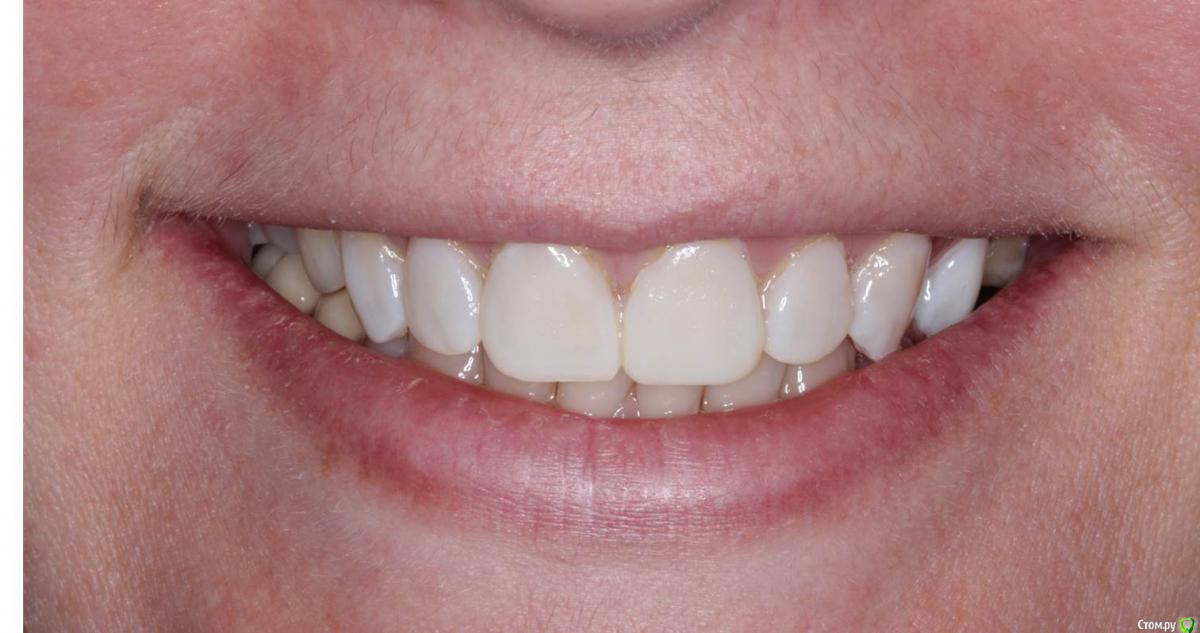

Сева северный Опубликовано 9 декабря, 2015 Поделиться Опубликовано 9 декабря, 2015 Ко мне обратилась молодая девушка, не довольная своей улыбкой. Был проведен этап планирования.... анализ улыбки ..(DSD), (wax up) и примерка (mock up)Проведенный этап...с мотивировал пациентку . 15 Ссылка на комментарий

Сева северный Опубликовано 11 декабря, 2015 Автор Поделиться Опубликовано 11 декабря, 2015 Почему не через зеркало?В принципе на вопрос уже ответили.... могу лишь добавить, что при (wax up) мы как правило воск добавляем, причем его слои, не всегда одинаковой толщины, поэтому темные зубы через (mock up) будет просвечиваться.Бывают варианты когда я наоборот не могу наносить воск+ мелкие косячки... в виде пор, фестончатых краев, небольшой ассимитрии. все это будет видеть пациент через зеркало. С расстояния.. 2-3 метра они с нивелируются. Я должен показать общую картину, именно улыбку. Сравните на прикрепленном примере... пришеечные косячки (mock up) которые я не стал исправлять, и как они не заметны на фото, с растояния 2 Ссылка на комментарий